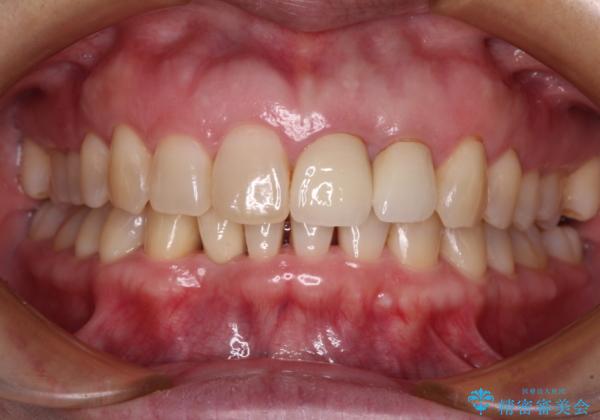

- 下顎前歯が抜けそうとのことで来院された患者様です。

初診の状態ではすぐにでも抜けそうな状態で、インプラントによる補綴治療を行うこととしました。

インプラント治療に際し、前歯の叢生に対する矯正治療を提案したところ、興味を持たれたので、インビザライン・ライトによる矯正治療を行うこととしました。

抜歯後にスペースができると恥ずかしいため、抜歯した歯を接着剤で固定した上で矯正治療を行い、その後インプラントやオールセラミッククラウンの装着を行うこととしました。